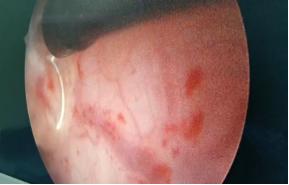

经尿道膀胱肿瘤等离子电切术:以病人的尿道为操作通路,置入等离子电切镜,将肿瘤切除后冲出,术后当天可正常下床活动、恢复饮食,避免了切口肿瘤种植的风险。在免去患者一刀之苦的同时,降低了肿瘤复发几率,极大的造福了膀胱肿瘤的患者。